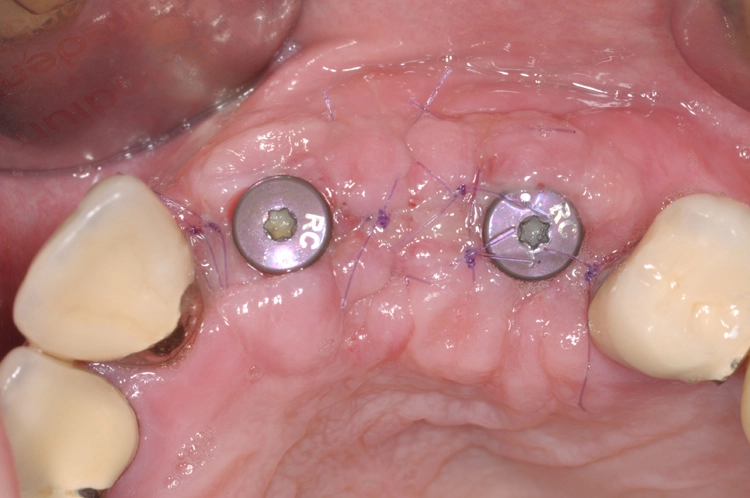

Die Abbildungen 11 und 12 dokumentieren das augmentative Relining, das zum Schutz vor Resorption und zur Konturaugmentation dienen soll. Dabei wurde eine Schicht bovines Knochenersatzmaterial (Straumann® XenoGraft) direkt auf den neu aufgebauten Knochen aufgetragen und mit Hilfe einer Kollagenmembran (Jason® membrane, Straumann) konturiert und vernäht. Damit legt man dem darunterliegenden neu aufgebauten Knochen einen Schutzpanzer an, der ihn einmal mehr vor Resorption schützt und die weitere Regeneration begünstigt.

Praxis Dr. Robert Würdinger